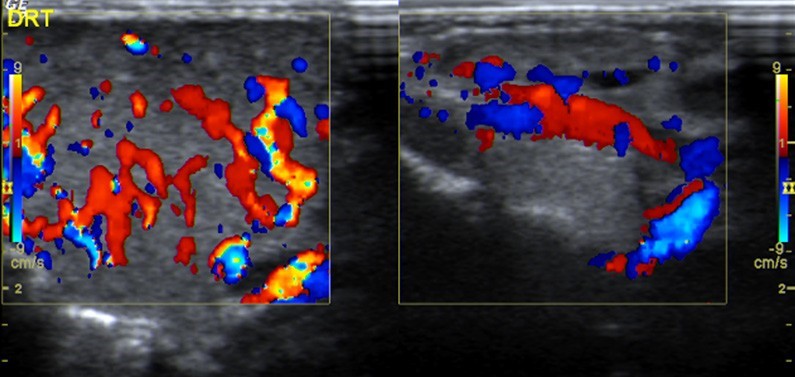

A ecografia de partes moles demonstrou a presença de massa heterogénea, bem delimitada, com contornos lobulados, correspondendo à glândula parótida com alteração da sua ecoestrutura e volume (Fig. 1), sem extensão ou invasão dos planos adjacentes passíveis de avaliação, intensamente vascularizada (Fig. 2), com vasos de grande calibre no seu interior quer arteriais quer venosos.

Figura 2: Ecografia de partes moles com Doppler: massa intensamente vascularizada, com vasos de grande calibre no seu interior.